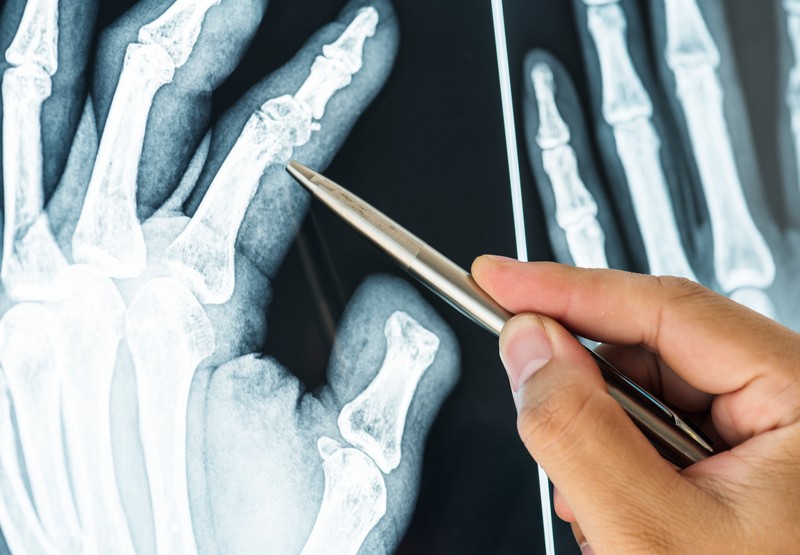

Для выявления хондромы проводят следующие обследования.

Следует подчеркнуть, что ранняя диагностика хондромы имеет ключевое значение для выбора адекватного лечения и улучшения прогноза для пациента.